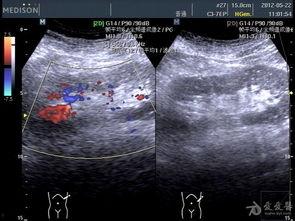

首先,得先给你科普一下什么是双肾B超。简单来说,双肾B超就是通过超声波来观察肾脏的一种检查方法。它可以帮助医生了解肾脏的大小、形态、位置以及内部结构,对于诊断肾脏疾病有着非常重要的作用。

现在,有了双肾B超在线视频,这些问题都迎刃而解了。你只需要在手机上下载一个专门的APP,注册账号,上传你的B超报告,就能在线观看专家的解读视频。这些视频通常由专业的医生团队制作,他们会详细地解释B超报告中的每一个细节,让你对自己的身体状况有更清晰的认识。